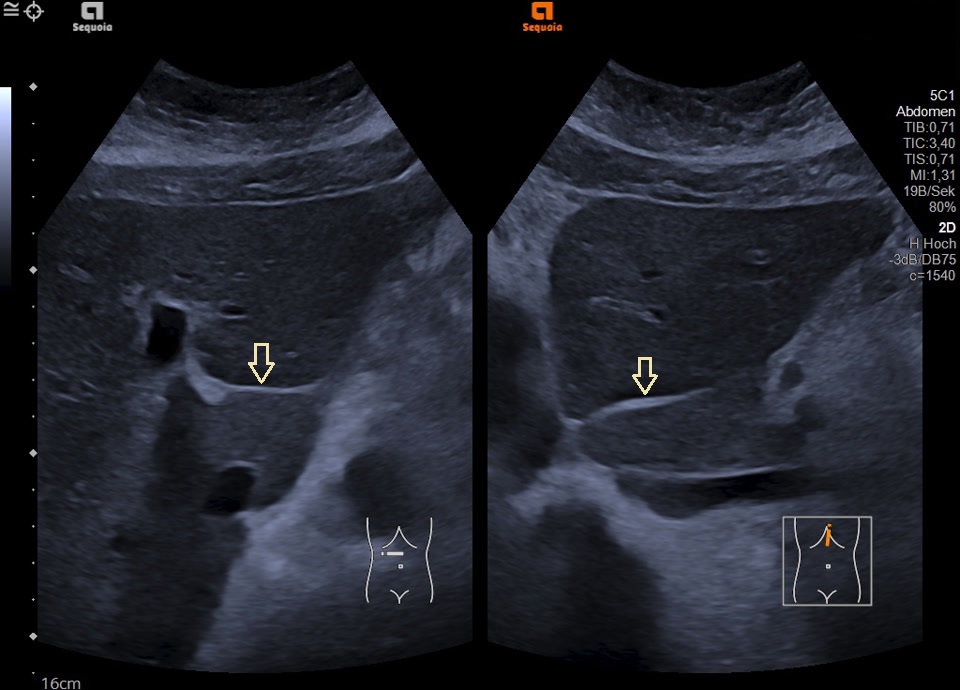

• Liver in midclavicular line

Normalbefund der Leber im Medioklavikularschnitt (mit im Bild ist die rechte Niere angeschnitten)